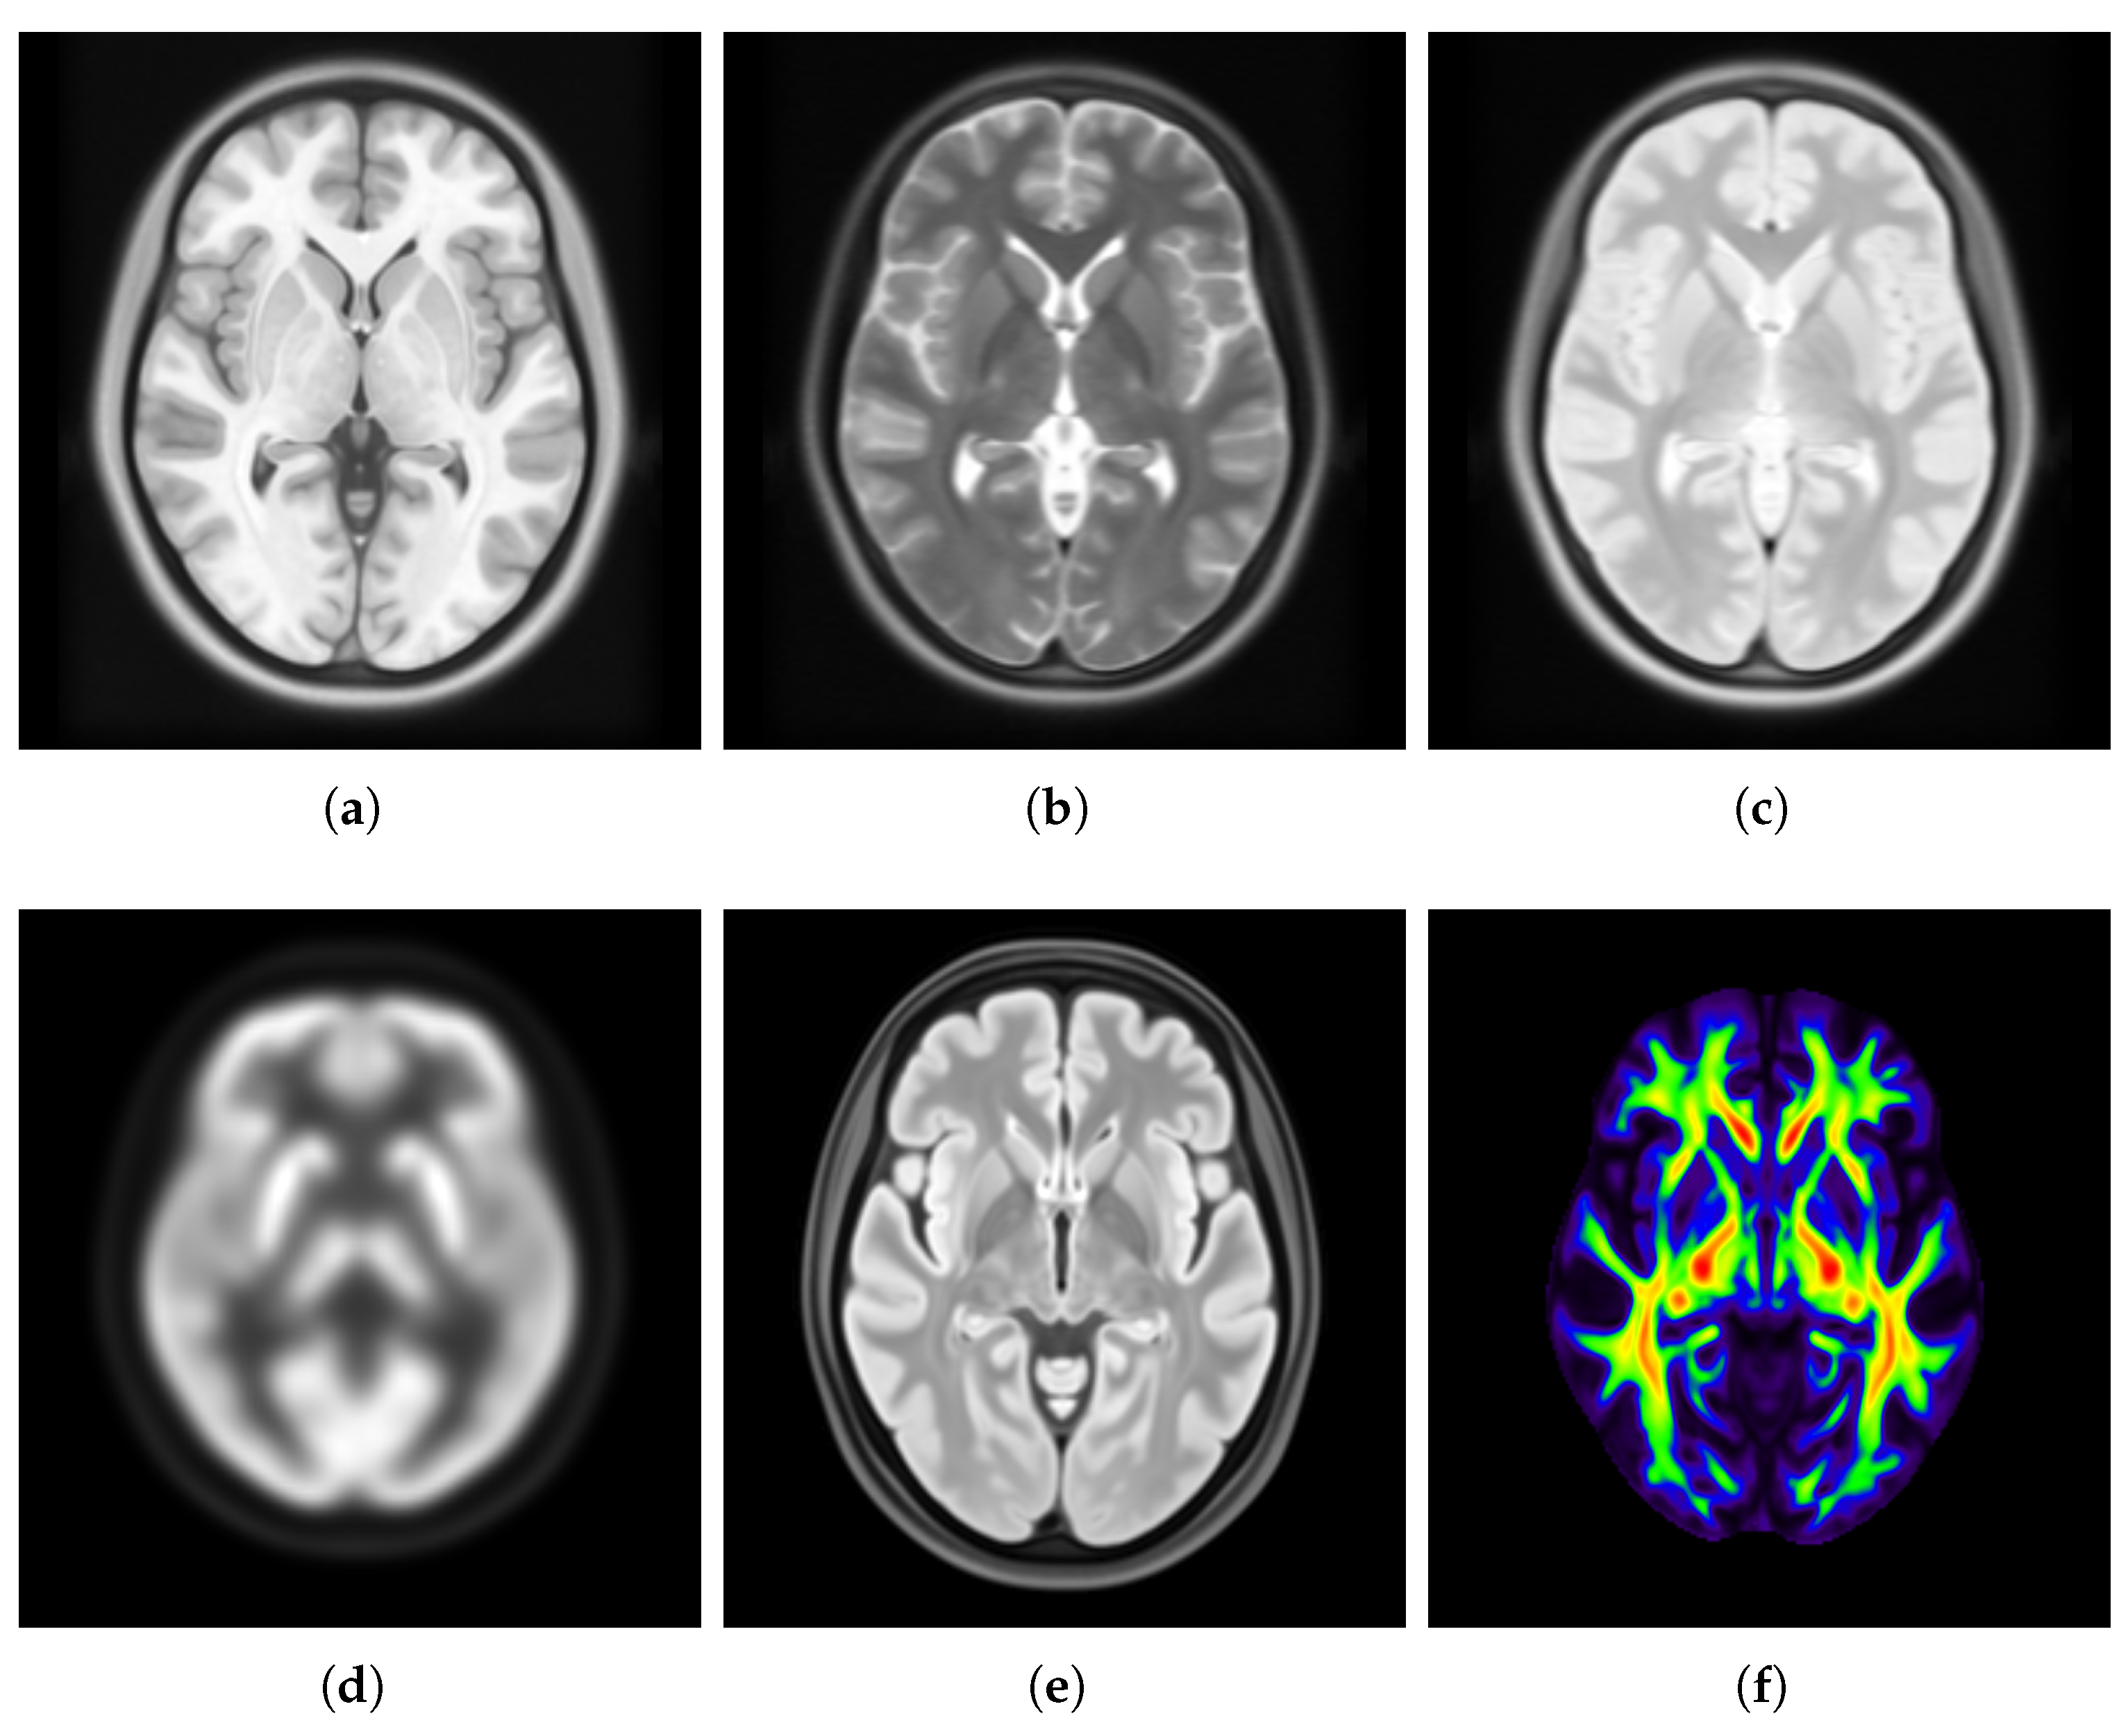

3.2.1. Spatial Normalization

3.2.2. Bias Field Correction

3.2.3. Denoising

3.2.4. Brain Extraction

3.2.5. Intensity Normalization